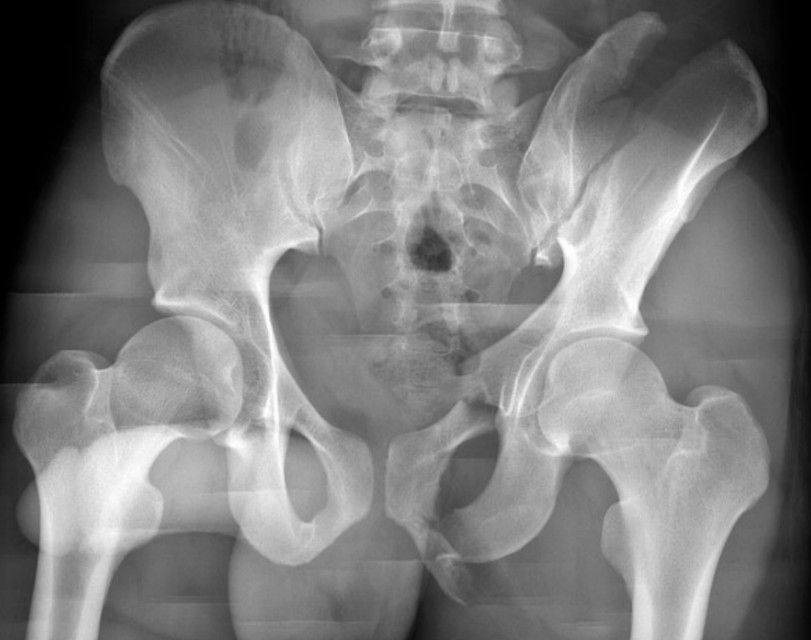

Pelvic trauma with haemorrhagic shock

A 34-year-old man is brought to a tertiary ED after being hit by a car while crossing the street.